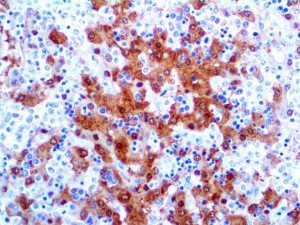

The first cytokines released are interleukin 1β (IL-1β) and tumor necrosis factor-α (TNF-α), which attract a variety of circulating white blood cells (WBCs) to the infection site, including neutrophils, monocytes, macrophages, and natural killer (NK) cells. This response, along with the antipathogenic chemicals released by these cells (i.e., complement), comprise the innate immune response. These cells directly attack the invading pathogen and also release additional cytokines, chief among them interleukin-1 and 6 (IL-6). IL-6 is essential for invoking the adaptive immune response, which calls T-cells, B-cells, and T helper (Th) cells to the infection site. IL-6 also stimulates further recruitment, proliferation and activation of macrophages.

It is the ICU physician who is most likely to witness one of the deadliest manifestations of the abnormal immunological response, the cytokine storm syndrome (CSS). This response is also referred to by some as the cytokine release syndrome (CRS). CSS is characterized by continuous activation and expansion of macrophage and lymphocyte populations, which secrete large amounts of cytokines, causing the cytokine storm. This massive cytokine release is akin to hemophagocytic lymphohistiocytosis (HLH) disease, a syndrome characterized by initial unchecked and persistent activation of cytotoxic T lymphocytes and NK cells.